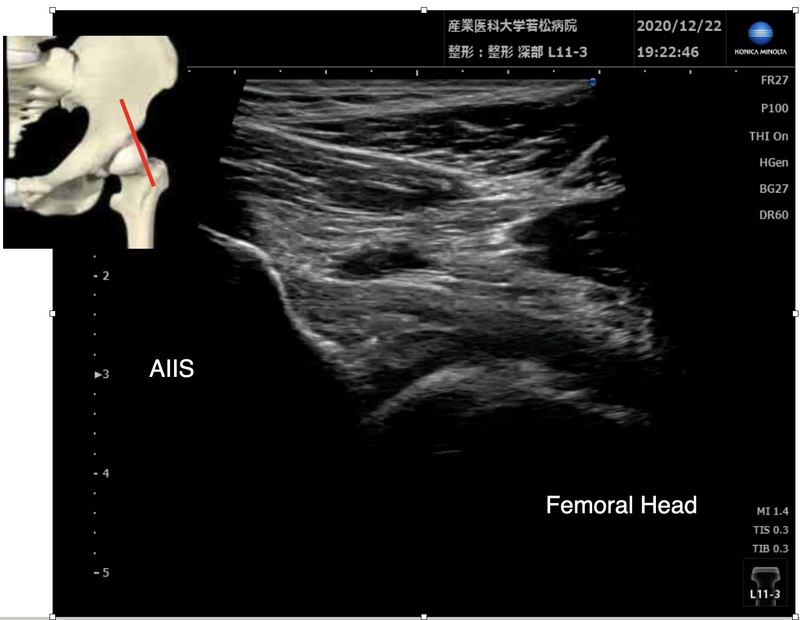

超音波ガイド下関節内ブロック

関節内注射のみ

1% カルボカイン 5ml

デカドロン 1.65mg

25Gの針

ドプラーで血管の位置を確認しておく